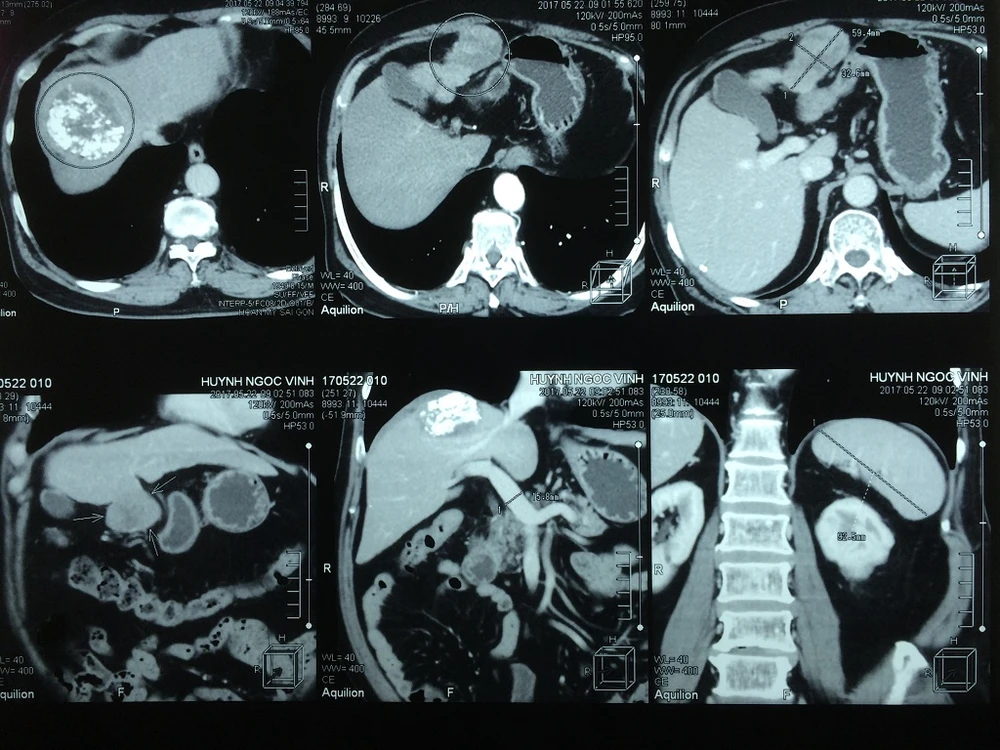

Hình ảnh hai khối u trong bụng bệnh nhân

Sau thủ thuật TACE, bệnh nhân được hẹn tái khám sau hai tháng để theo dõi, qua chụp MSCT cho thấy khối u ngấm thuốc tốt, không có dấu hiệu tiến triển bệnh. Sau đó, bệnh nhân được hẹn tái khám mỗi 3 tháng, đến tháng 5-2017, trên hình ảnh MSCT, ngoài khối u gan đã được điều trị, các BS phát hiện thêm một khối u mới bên gan trái, kích thước 5x7 cm, qua hội chẩn nhận thấy vị trí u thuận lợi cho việc phẫu thuật nội soi cắt bỏ u.